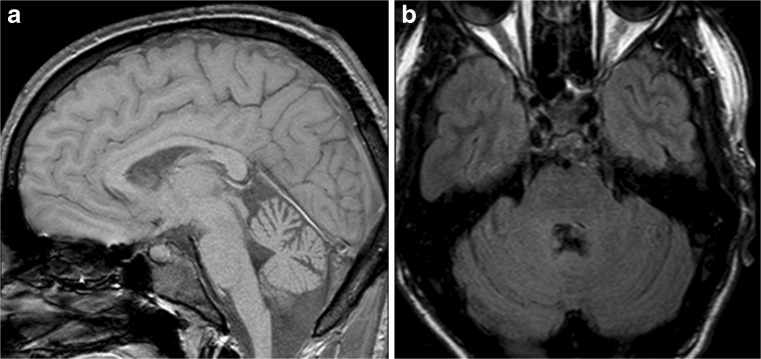

Structural Brain Imaging and [18F] FDG PET

The imaging data are summarized in Table 1 and are shown in Figs. 2, 3, 4, 5, 6, 7, and 8. Brain MRI revealed atrophy of the vermis and supratentorial white matter hyperintensities (WMH) in patients III:1 and III:2 and to a lesser degree in the index case (Figs. 2, 3, and 5). These WMH were particularly widespread in III:1 (Fig. 2). The index case was not affected by any other comorbidity usually associated with WMH, suggesting that these abnormalities may be an underlying feature of SCA19/22. WMH were not evident in the youngest patient (V:1). [18F] FDG PET revealed hypometabolism in the entire cerebellum, thalamus, prefrontal cortex (PFC), and parietal regions of the index case (IV:1) (Fig. 6). Her mother had reduced glucose metabolism not only in the PFC but also in the vermis as wells as in the motor and temporal cortex (Fig. 4). The youngest patient (V:1) had hypometabolism in the PFC, parietal, and inferior temporal regions but surprisingly not in the cerebellum (Fig. 8). In the latter structure, atrophy of the vermis was evident (Fig. 7).

Fig. 2.

Brain MRI of patient III:1. a Midsagittal T2-weighted image displays moderate vermis atrophy. b Coronal T2-weighted image showing periventricular and deep white matter hyperintensities

Fig. 3.

Brain MRI of patient III:2. a Mild vermis atrophy is evident on this midsagittal T2-weighted image. b Coronal T2-weighted image displays deep white matter hyperintensities

Fig. 5.

Brain MRI of patient III:2. a Midsagittal T2-weighted image shows mild vermis atrophy. b Punctate white matter hyperintensities in the frontal lobe are evident in the coronal T2-weighted image

Fig. 7.

Brain MRI of patient V:1. a Midsagittal and coronal T1-weighted image. b Mild cerebellar atrophy